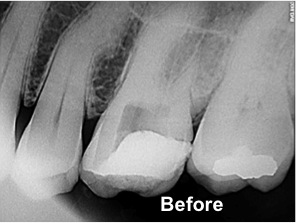

The patient at this stage has to take a decision to either save the tooth or extract it.Saving means getting root canal treatment done which involves physical removal of the infected pulp or the dead tissue as the case might be. The next step is towiden and shape the canals,disinfect it and fill it with an inert material like gutta-percha. Subsequently the access cavity is filled with a suitable filling material. Now this tooth functions as any normal tooth except that there is no moisture supply to this tooth. This makes the tooth dry and brittle. Hence to reinforce it, a cap may be given which restores the tooth to normal anatomy and function.